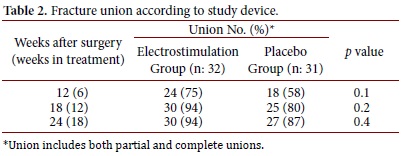

Results: Healing observed at week 12 was 75% vs. 58% (p= 0.1); at week 18, it was 94% vs. 80% (p= 0.15); and at week 24, it was 94% vs. 87% (p= 0.43) for the device group and the placebo group, respectively.

Patients whose X-rays showed union (complete or partial) were grouped together and compared against patients with non-union X-rays. As shown in Table 2, healing observed at week 12 was 75% vs. 58% (p= 0.1), at week 18: 94% vs. 80% (p= 0.15), and at week 24: 94% vs. 87% (p= 0.43) for device group and placebo group, respectively. This shows a non-statistically significant difference in the time in which fractures progress to union. The risk of non-union was lower for the electromagnetic stimulation group at the three measure points: week 12 (relative risk for non-union, 0.60; 95% CI, 0.29 to 1.24), week 18 (RR: 0.32; 95% CI, 0.07 to 1.48) and week 24 (RR: 0.70; 95% CI, 0.17 to 2.88).

In this study, bone healing was achieved faster when patients were exposed to an electromagnetic field compared to the placebo group. At week 12, unions were achieved in 75% vs. 58% (p= 0.1), and at week 18, unions were achieved in 94% vs. 80% (p= 0.15). This shows a trend of more patients having their fracture healed in less time when using the electromagnetic field as coadjuvant. Nevertheless, this was not a statistically significant difference. At the end, after 18 weeks of electromagnetic therapy or 24 weeks since the fracture day, no differences were identified between both groups, 94% vs. 87% (p= 0.43). The difference in bone healing time between groups decreases as weeks pass until they become virtually the same at week 24.